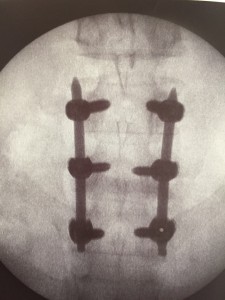

Consiste en la colocación de tornillos pediculares que se unen entre sí mediante barras. Normalmente hablamos de una artrodesis de un nivel cuando implica la fusión de 2 vértebras lumbares. En este caso utilizaremos 4 tornillos pediculares y 2 barras que unen los tornillos dos a dos de manera simétrica. Cuando hablamos de artrodesis de dos niveles, nos referimos a la fusión de 3 vértebras lumbares. En este caso utilizaremos 6 tornillos pediculares y 2 barras que unen los tornillos dos a dos de manera simétrica. El material implantado es de una aleación de titanio de grado médico, biocompatible.Esta técnica puede realizarse mediante cirugía abierta o bien mediante cirugía mínimamente invasiva. Se realiza mediante controlo radioscópico estricto. En este último caso, las incisiones son menores, con menor lesión muscular, mejor recuperación y alta hospitalaria en 2-3 días.